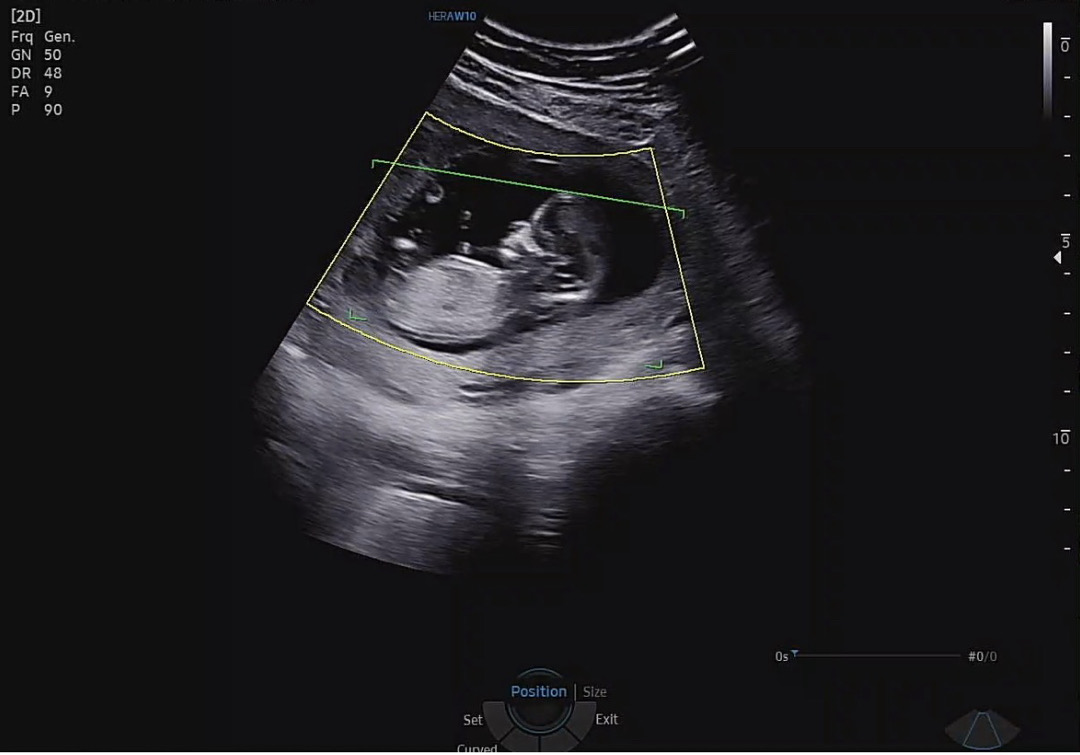

12주차 성별 예측 부탁드려요!!

12주차 초음파 사진인데 명확하진 않은것 같지만 부탁드려요!